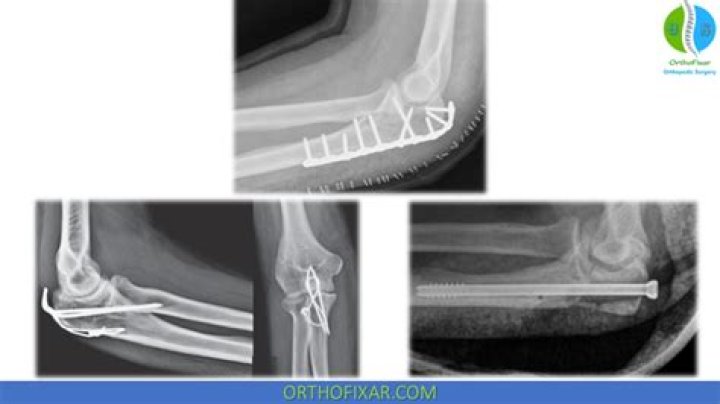

Some olecranon fractures can be treated by being casted or placed in a splint to hold the elbow in place while the bone heals. Surgery may be indicated if the elbow is displaced or if the fracture is open. Displaced fractures are treated operatively by internal fixation using wires, screws or plates.

Open reduction and internal fixation (ORIF) is a type of surgery used to stabilize and heal a broken bone. You might need this procedure to treat your broken elbow. The elbow joint is a hinge type of joint composed of 3 bones.